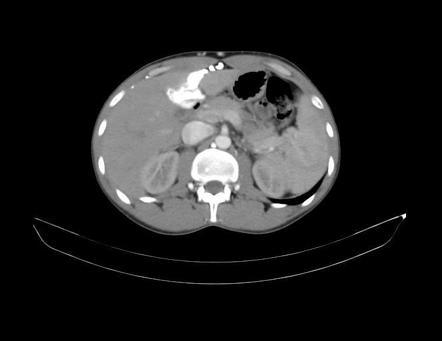

Normal liver attenuation

40-60 HU; >75 HU = hyperattenuating; hypoattenuating = less than spleen on NECT or 25 HU less than spleen on CECT